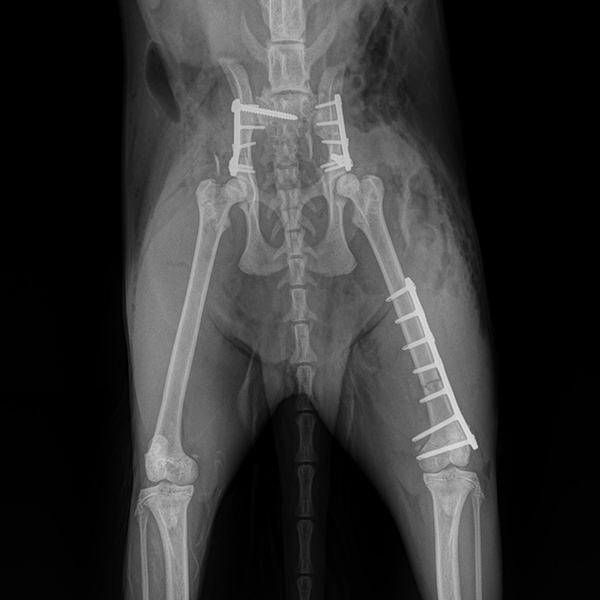

Fracture Treatment in Small Breeds:

Experience of 100 Cases

CrCL Ruptures in Small Breeds:

Osteotomies or extra capsular repair

CrCL Ruptures in Small Breeds: Should we use osteotomies instead of extra capsular repair?

TTA RAPID®

Learn how to perform CCL Repair with TTA RAPID®

Tiny TTA RAPID®

Learn how to fix CCL Ruptures in Tiny Animals with the Tiny TTA RAPID® System